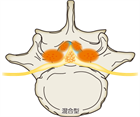

1. 馬尾型もしくは混合型の腰部脊柱管狭窄(LSS)による間欠跛行患者にはリマプロスト投与を推奨する(推奨度2)